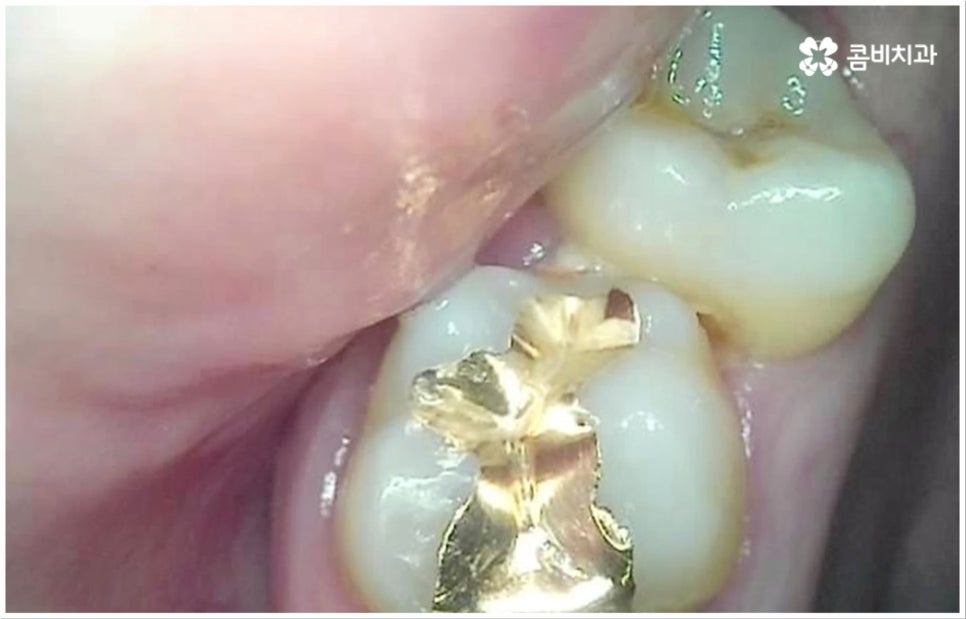

치아 가장 안 쪽의 신경관까지 세균으로 오염되었다면 신경 치료를 통해 변성된 신경을 제거하고 신경관(근관)을 소독 밀봉한 후 남아 있는 자연 치아를 보호하기 위해 크라운을 씌우게 되는데, 환자분들 중에 이러한 보철치료 후 더이상 시리거나 쑤시는 등의 충치 통증 이 느껴지지 않아 해당 치아에 앞으로 남은 평생 아무런 문제가 생기지 않을 거라 오해하시는 분들이 더러 있어요. 하지만 보철물에도 수명이 있기 때문에 주기적으로 마모 정도 및 미세 파절 여부를 검진한 후 필요시 교체해야 하며 시간이 지나면서 보철물과 치아 사이 미세한 틈이 발생할 수 있어 그 사이로 세균이 침입한다면 2차 충치가 유발될 가능성도 있으니 주의하실 필요가 있습니다.

통상적으로 보철물의 주기는 10년이라고 알려져 있으나 환자분들의 평상시 식습관이나 구강위생 관리 여부 등에 따라 자세한 상황은 달라질 수 있기 때문에 지속적인 관찰을 통해 파절, 탈락, 2차 충치 등의 문제가 생기지 않도록 관리하는 것이 중요하다고 할 수 있어요. 특히 신경이 제거된 상태라면 충치 통증 을 느끼지 못할 것이므로 혹여 치아를 살리기 어려울 정도로 2차 충치가 심각해 질 때까지 발견하지 못하는 상황이 생기지 않도록 정기 검진을 철저하게 하고 스케일링 치료를 통해 구강 내부를 청결하게 유지해 주는 것이 필요할 거예요.